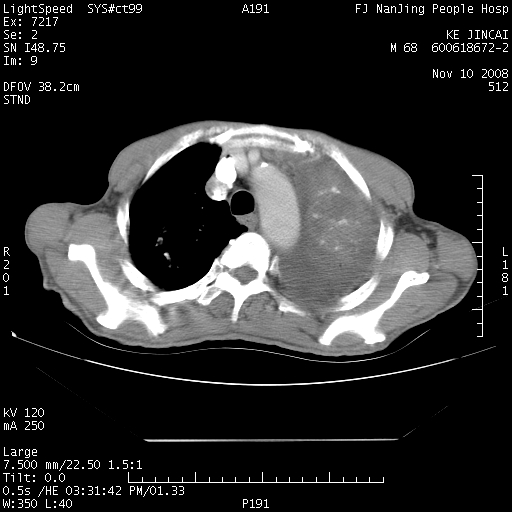

是个很有看头的病例,咋人气那么不旺?没多少人兴趣呢?这个病例几大怪:1   恶性肿瘤侵犯心肌左房怪,心肌一般不会被恶性肿瘤侵犯吧?2   左下肺均匀实变怪,内无含气,有别一般不张实变,含气肺泡完全为液体取代,而非一般不张实变的肺萎陷,冷不丁还以为是肿大的脾脏3   肿瘤本身怪,像tb肺不张4   这么有看头的病例没人气怪。呵呵。

追查病史,咳嗽,患者无发热,血象不高。据说2年前胸片检查怀疑肺ca曾行纤支镜检查,病理未见到癌细胞。无确切资料。

左肺恶性肿瘤侵犯肺动脉,左心房内瘤栓,胸膜转移。